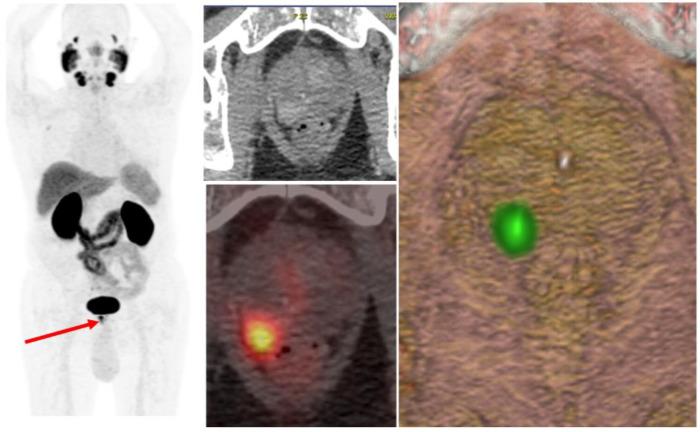

Prostate-specific membrane antigen positron emission tomography/computed tomography (PSMA-PET/CT) has emerged as a game-changing imaging modality in prostate cancer, offering superior sensitivity and specificity compared to conventional imaging techniques. Its increasing adoption has significantly influenced radiotherapy decision-making, yet its true clinical impact remains under investigation. This narrative review explores the role of PSMA-PET/CT in guiding radiotherapy decisions across different clinical scenarios, from primary treatment planning to biochemical recurrence and oligometastatic disease. We assess its impact on target delineation, treatment modifications, and overall patient management while addressing existing knowledge gaps.

前列腺特异性膜抗原正电子发射断层扫描/计算机断层扫描(PSMA-PET/CT)已成为前列腺癌领域一项具有变革性的成像模态,与传统成像技术相比,具有更高的敏感性和特异性。其应用的日益广泛显著影响了放疗决策,但它的真正临床影响仍在研究中。这篇叙述性综述探讨了PSMA-PET/CT在不同临床场景中指导放疗决策的作用,从初始治疗计划到生化复发和寡转移疾病。我们在解决现有知识空白的同时,评估其对靶区勾画、治疗调整和整体患者管理的影响。